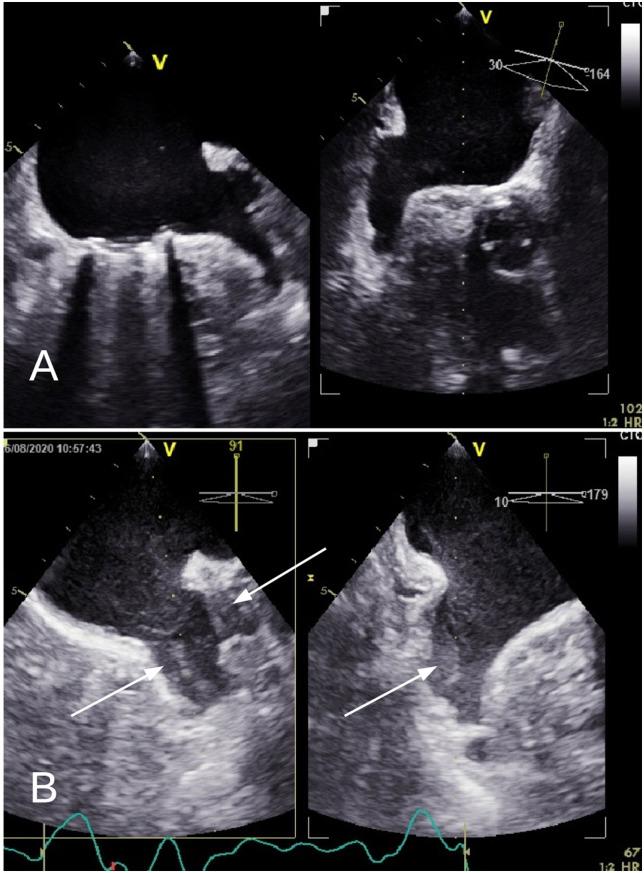

We present the case of a 66-year-old female with a history of AF and mechanical aortic and mitral valve replacement, which was admitted to the hospital complaining of dizziness and unsteady gait. A computerized tomography scan of the brain confirmed the diagnosis of embolic stroke. Two years later, the patient complained of sudden onset of chest pain, accompanied by electrocardiographic abnormalities and elevated high-sensitivity troponin T. Emergency cardiac catheterization revealed embolic myocardial infarction with distal occlusion of the obtuse marginal artery. Again, 2 years later, the patient suffered a new cerebral embolic event. Given the adequate anticoagulation therapy throughout almost the entire clinical course, percutaneous left atrial appendage closure was proposed as an adjunct to vitamin K antagonist treatment. Notably, intraprocedural transoesophageal echocardiography revealed the presence of a previously undetected left atrial appendage thrombus, thus an embolic protection device was used during the procedure, which was successfully carried out without complications.

我们报告一例66岁女性患者,有房颤病史,接受过机械主动脉瓣和二尖瓣置换术,因头晕和步态不稳入院。脑部计算机断层扫描确诊为栓塞性中风。两年后,患者主诉突发胸痛,伴有心电图异常及高敏肌钙蛋白T升高。急诊心脏导管检查显示为栓塞性心肌梗死,钝缘支动脉远端闭塞。又过了2年,患者发生了一次新的脑栓塞事件。鉴于几乎在整个临床过程中都进行了充分的抗凝治疗,建议采用经皮左心耳封堵术作为维生素K拮抗剂治疗的辅助手段。值得注意的是,术中经食管超声心动图显示存在一个先前未被发现的左心耳血栓,因此在手术过程中使用了栓塞保护装置,手术成功实施,未出现并发症。